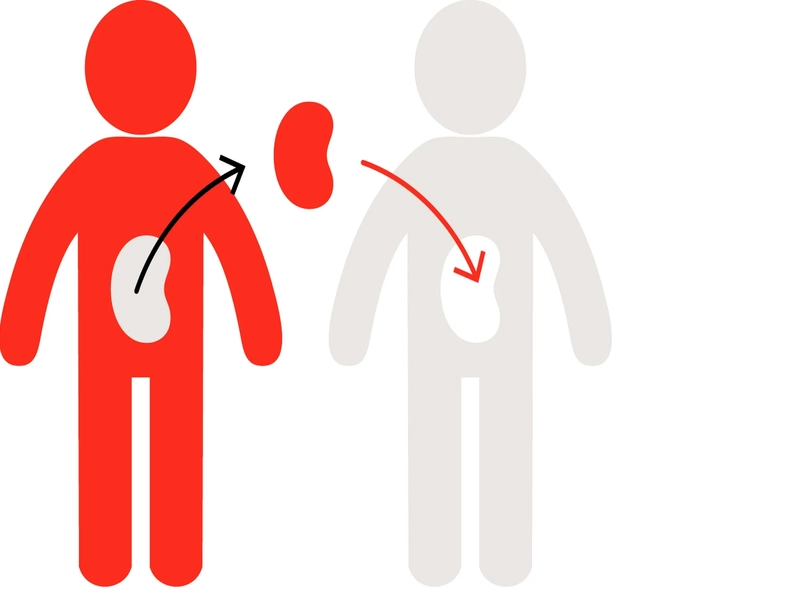

پیوند کلیه، عمل جراحی پیشرفتهای است که در آن، کلیه بیمار یا آسیبدیده با یک کلیه سالم از یک اهداکننده (زنده یا متوفی) جایگزین میشود. این روش درمانی حیاتی، به افرادی که به دلیل بیماریهای مزمن کلیوی یا آسیبهای شدید، عملکرد طبیعی کلیه خود را از دست دادهاند، فرصت زندگی دوباره میبخشد. کلیهها، اندامهای لوبیایی شکلی هستند که در دو طرف ستون فقرات قرار دارند و وظیفه تصفیه خون از مواد زائد و حفظ تعادل مایعات و الکترولیتهای بدن را بر عهده دارند. در صورت نارسایی کلیه، این عملکردها مختل شده و منجر به عوارض جدی و حتی مرگ میشوند. پیوند کلیه، با جایگزینی کلیه آسیبدیده با یک کلیه سالم، به این بیماران امکان میدهد تا از دیالیز رهایی یابند و کیفیت زندگی خود را بهبود بخشند.

پیوند کلیه میتواند از یک اهداکننده زنده یا متوفی صورت گیرد. در پیوند از اهداکننده زنده، یکی از کلیههای یک فرد سالم به بیمار پیوند زده میشود. اهداکننده میتواند یکی از اعضای خانواده، دوست یا حتی یک فرد غریبه باشد. در پیوند از اهداکننده متوفی، کلیههای یک فرد دچار مرگ مغزی به بیماران نیازمند پیوند زده میشود. این نوع پیوند به دلیل کمبود اهداکنندگان کلیه، با محدودیتهایی مواجه است. با این حال، پیوند کلیه از هر دو نوع، میتواند به بیماران مبتلا به نارسایی کلیوی، زندگی جدیدی ببخشد و امید به آینده را در آنها زنده کند.

پیوند کلیه به دو صورت اصلی انجام میشود: پیوند از اهداکننده زنده و پیوند از اهداکننده متوفی.

- در پیوند از اهدا کننده زنده، یکی از کلیههای سالم یک فرد زنده به بیمار نیازمند پیوند زده میشود. این نوع پیوند معمولاً نتایج بهتری نسبت به پیوند از اهداکننده متوفی دارد، زیرا کلیه اهداکننده قبل از پیوند به طور کامل ارزیابی میشود و خطر رد پیوند کمتر است. همچنین، در این نوع پیوند، زمان انتظار برای دریافت کلیه کاهش مییابد، زیرا نیازی به انتظار در لیست انتظار پیوند نیست.

- در پیوند از اهدا کننده متوفی، کلیههای یک فرد دچار مرگ مغزی به بیماران نیازمند پیوند زده میشود. این نوع پیوند به دلیل کمبود اهداکنندگان کلیه، با محدودیتهایی مواجه است و بیماران ممکن است مجبور باشند مدت زمان طولانی در لیست انتظار پیوند بمانند. با این حال، پیوند از اهدا کننده متوفی نیز میتواند یک گزینه درمانی مؤثر باشد، به خصوص برای بیمارانی که اهدا کننده زنده ندارند. در هر دو نوع پیوند، هدف نهایی بهبود کیفیت زندگی و افزایش طول عمر بیمار است.